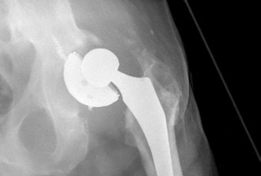

For anyone wondering about Acetabular Revision: Solving Challenges Post Two-Stage Arthroplasty, A **title acetabular revision** is a complex procedure addressing issues like septic loosening, dislocation, and significant osteolysis in total hip arthroplasty. For a 71-year-old male with a dislocated left THA due to infection and periacetabular bone loss, treatment involved a two-stage exchange followed by revision with a press-fit hemispherical cup and screw fixation.

These defects can typically be managed with a hemispherical, highly porous metal (tantalum or titanium foam) multi-hole acetabular component. The porous metal provides a high coefficient of friction for initial scratch fit and an optimal scaffold for biologic ingrowth. Particulate allograft may be used to fill contained cavitary defects prior to cup insertion. Multiple screws are placed into the safe zones of the ilium and ischium to maximize initial stability.